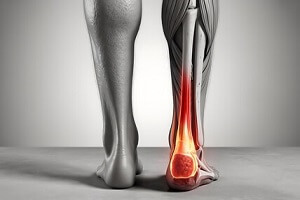

Le tendon d’Achille est le tendon le plus large et le plus résistant de notre corps. Situé à l’arrière de la cheville, il relie les muscles du mollet (gastrocnémiens et soléaire) à l’os du talon (calcanéum). C’est lui qui nous permet de marcher, courir, sauter, ou encore nous tenir sur la pointe des pieds.

Malgré sa puissance, ce tendon peut s’abîmer avec le temps ou à cause de contraintes excessives : on parle alors de tendinopathie d’Achille. Cette pathologie peut toucher deux zones :

- la partie centrale du tendon, on parle alors de tendinopathie corporéale,

- ou son point d’attache sur le talon, appelée tendinopathie d’insertion.